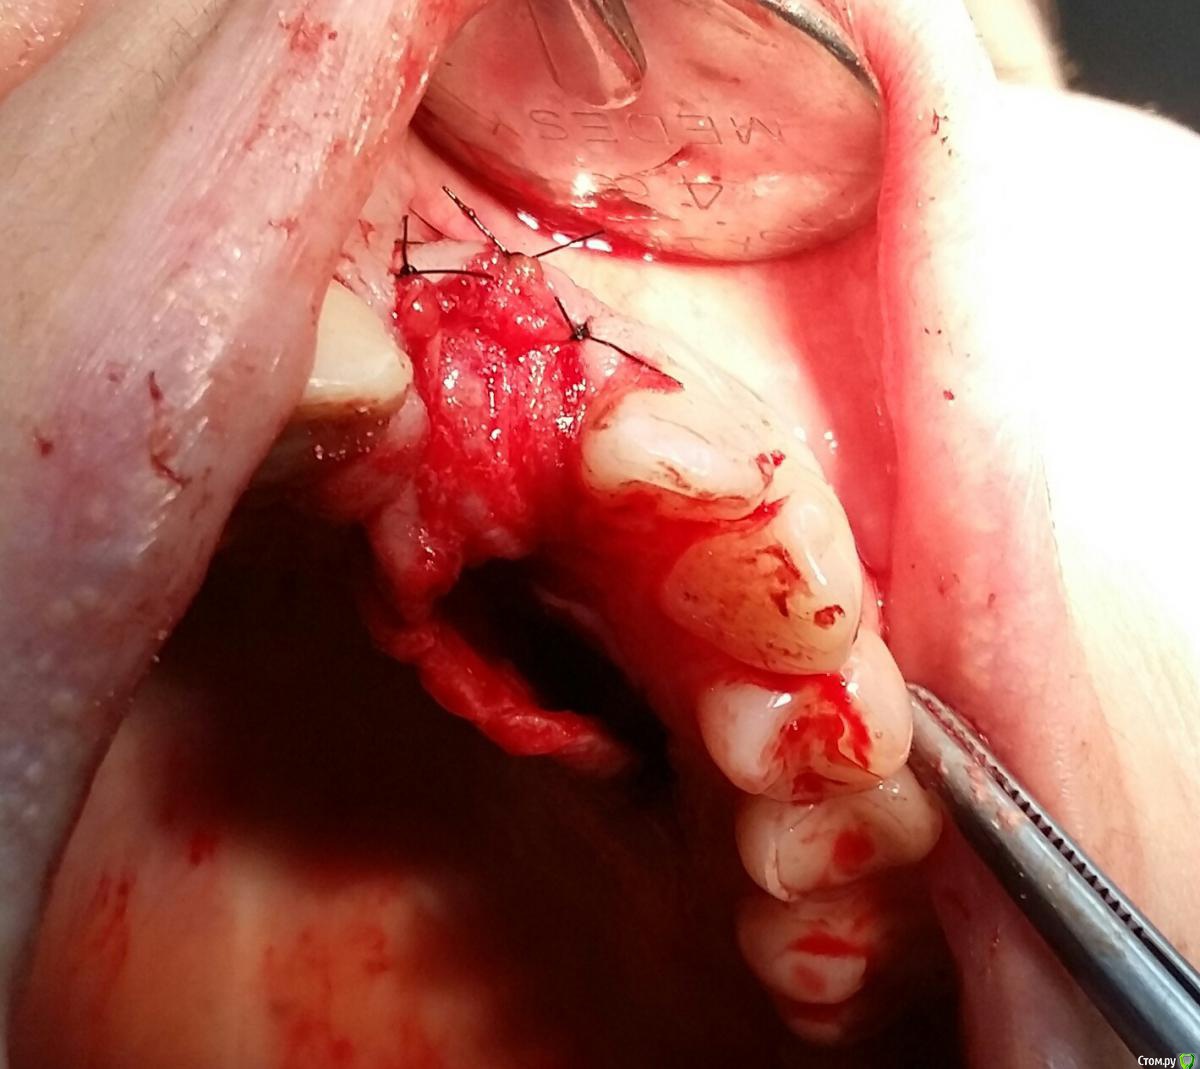

Kostoprav Опубликовано 8 ноября, 2017 Поделиться Опубликовано 8 ноября, 2017 заранее извиняюсь за качество фотографийдумал сделать все в один этап но торка ожидаемого не получил, поэтому пришлось накрыть винт випом.(материал osteobiol putyy) мне он очень понравиля ,удобный в работе. 17 Ссылка на комментарий

Kostoprav Опубликовано 8 ноября, 2017 Автор Поделиться Опубликовано 8 ноября, 2017 (изменено) putty перевод с английского как замазка, с випом больше шансов что он выживет поскольку есть питающая ножка, период наблюдения приблизительно год Изменено 8 ноября, 2017 пользователем Kostoprav Ссылка на комментарий

Kostoprav Опубликовано 8 ноября, 2017 Автор Поделиться Опубликовано 8 ноября, 2017 Торк был не достаточный для временной реставрации. Около 20. Я не рискнул.Срезы если найду выложу, хотя там ситуация стандартная ничего из ряда вон выходящего Ссылка на комментарий